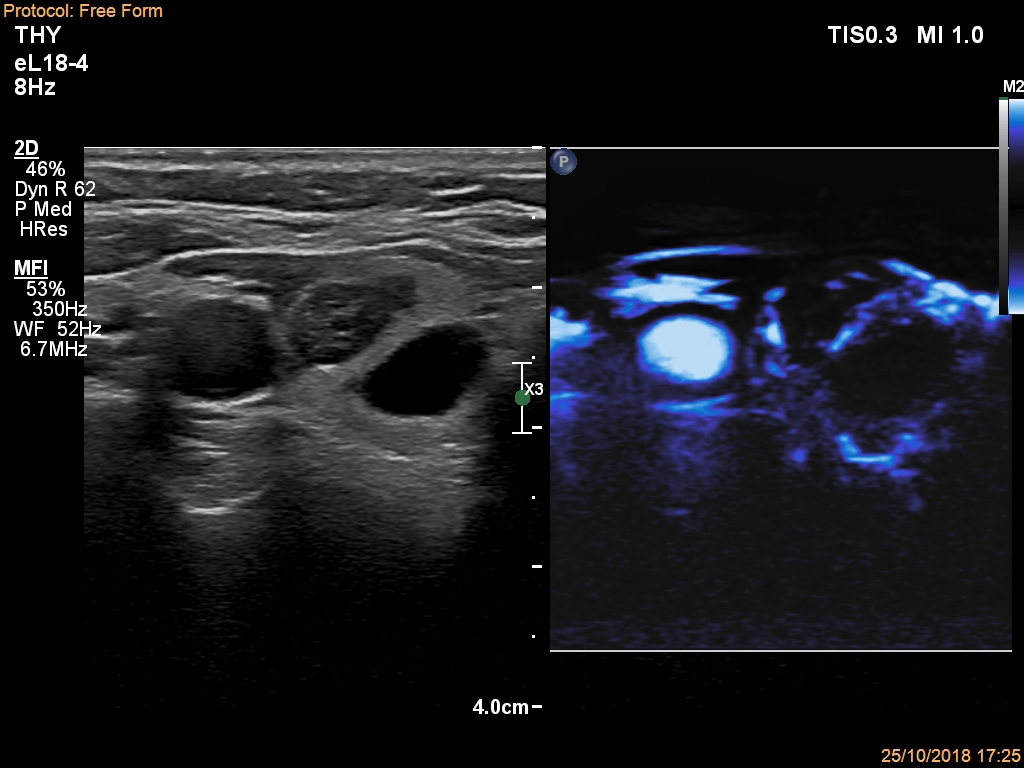

Ultrasonography. The thyroid was echonormal and had multiple nodules. There were cystic areas, an almost completely cystic nodule, and a dominantly solid nodule in the right lobe. The left lobe had three lesions. The upper solid lesion was the one we treated 16 years ago. The middle lesion was a dominantly solid while the lower one seemed to be a pure cyst. The dimensions of the nodule which has been treated with sclerotherapy were 10x11x13 mm (width, depth and length, respectively). There was a large cystic nodule in the upper pole of the left lobe. The lesion showed relatively large hyperechogenic granules. There were multiple enlarged lymph nodes lateral to the left lobe, two of largest were cystic.